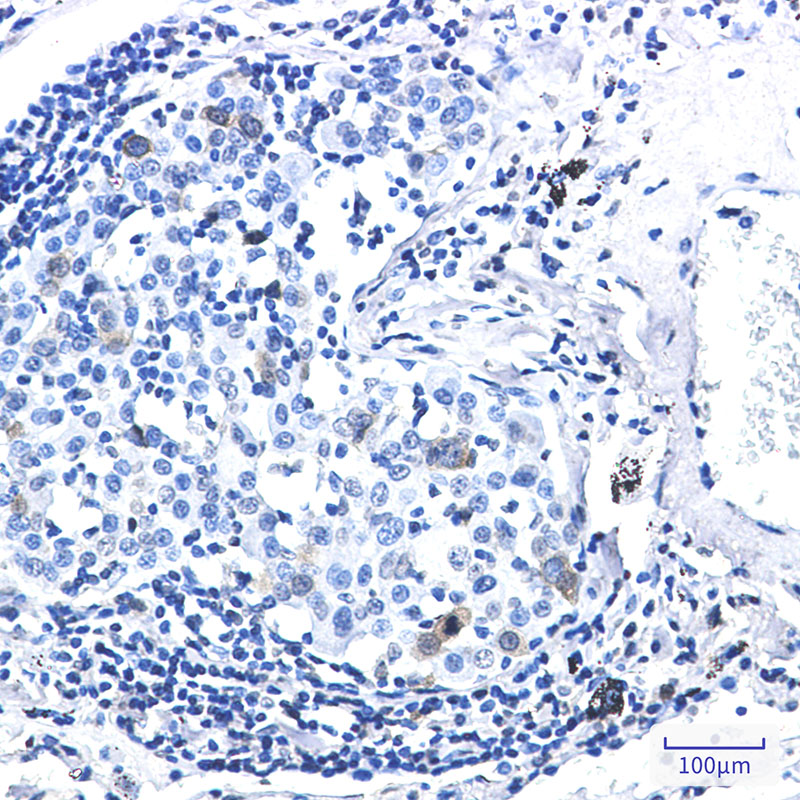

- Immunohistochemistry analysis of paraffin-embedded Human lung cancer using Cdk1/2 (Phospho-Thr14) antibody.High-pressure and temperature Sodium Citrate pH 6.0 was used for antigen retrieval.